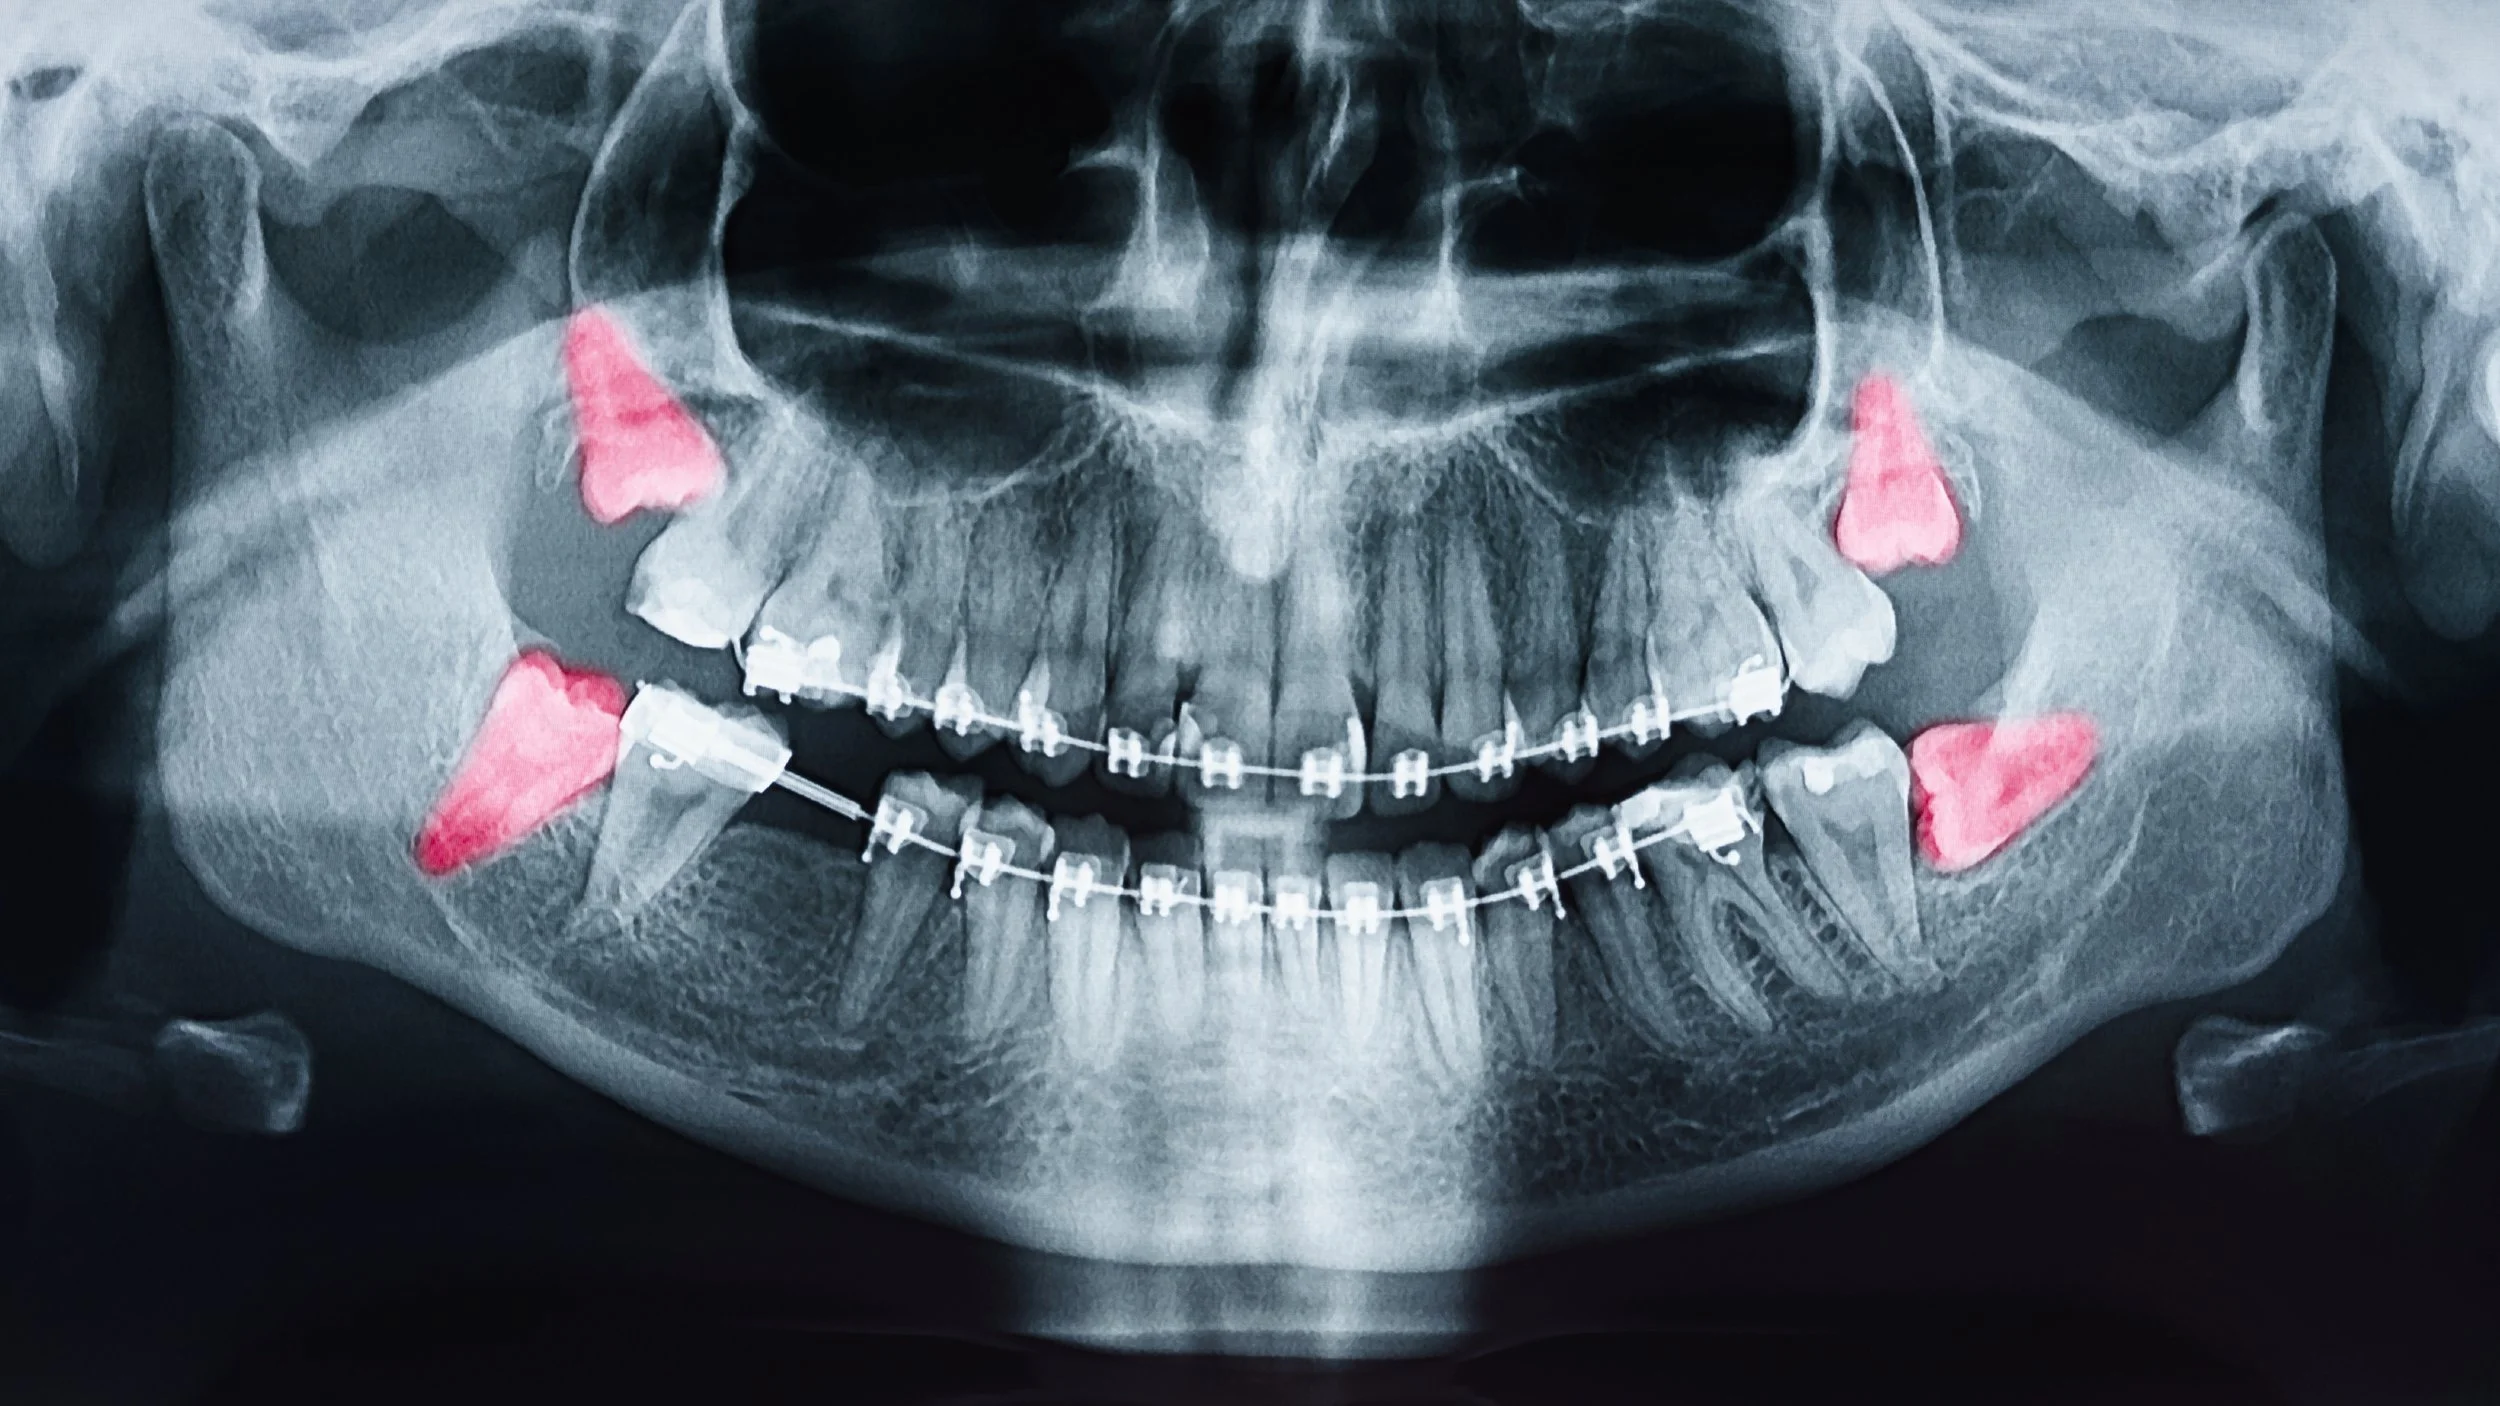

Your first visit includes a review of your medical history and dental X-rays to assess the size, shape, and position of your wisdom teeth. Based on this evaluation, your dentist or oral surgeon will discuss anesthesia options and what to expect during the extraction process.